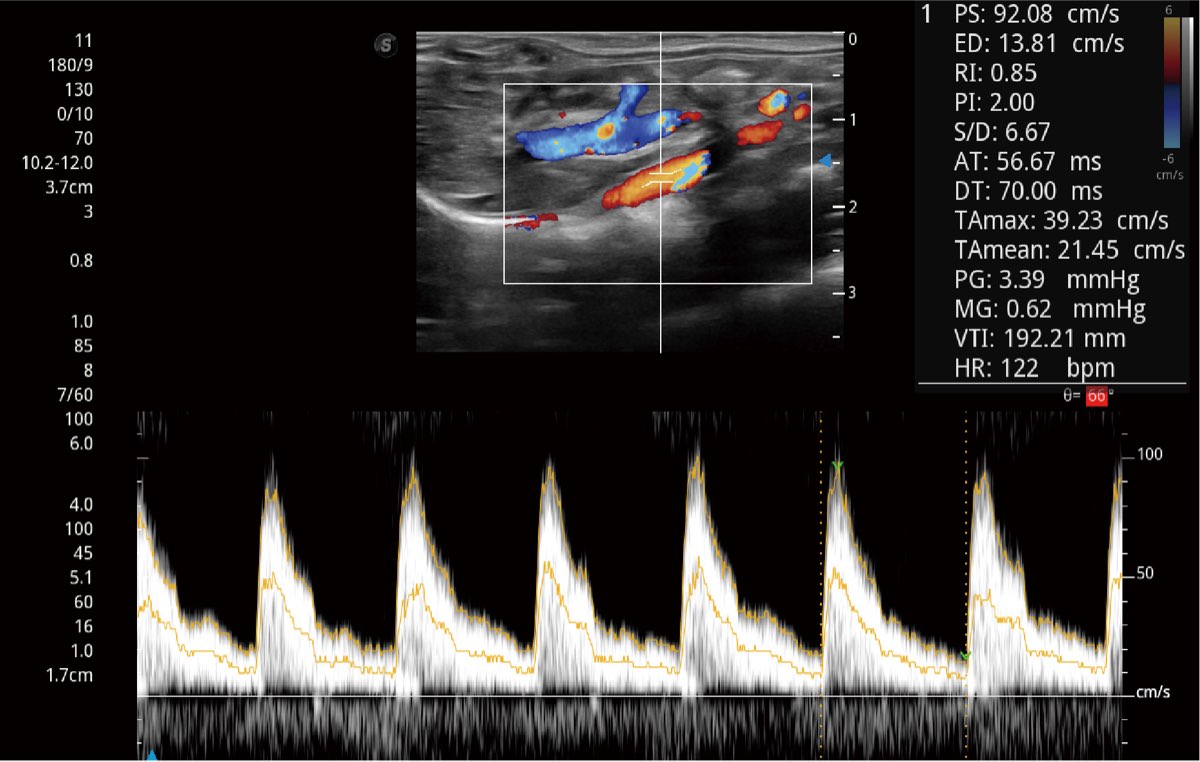

Przy pracach nad aparatem ProPet 60 uwzględniono najważniejsze preferencje i potrzeby weterynarzy, oferując finalnie przystępne cenowo i odpowiednio wyważone połączenie znakomitej precyzji klinicznej, zwiększonej wydajności i przemyślanego przebiegu pracy, niezastąpione w codziennej praktyce weterynaryjnej. Dzięki dostępowi do pełnej gamy głowic HD rozwiązanie to spełnia wszystkie potrzeby w zakresie obrazowania, umożliwiając wykonywanie badań jamy brzusznej, małych narządów, ortopedycznych, badań podczas rozrodu, a nawet badań serca i klatki piersiowej, a to wszystko przy doskonałym stosunku jakości do ceny.